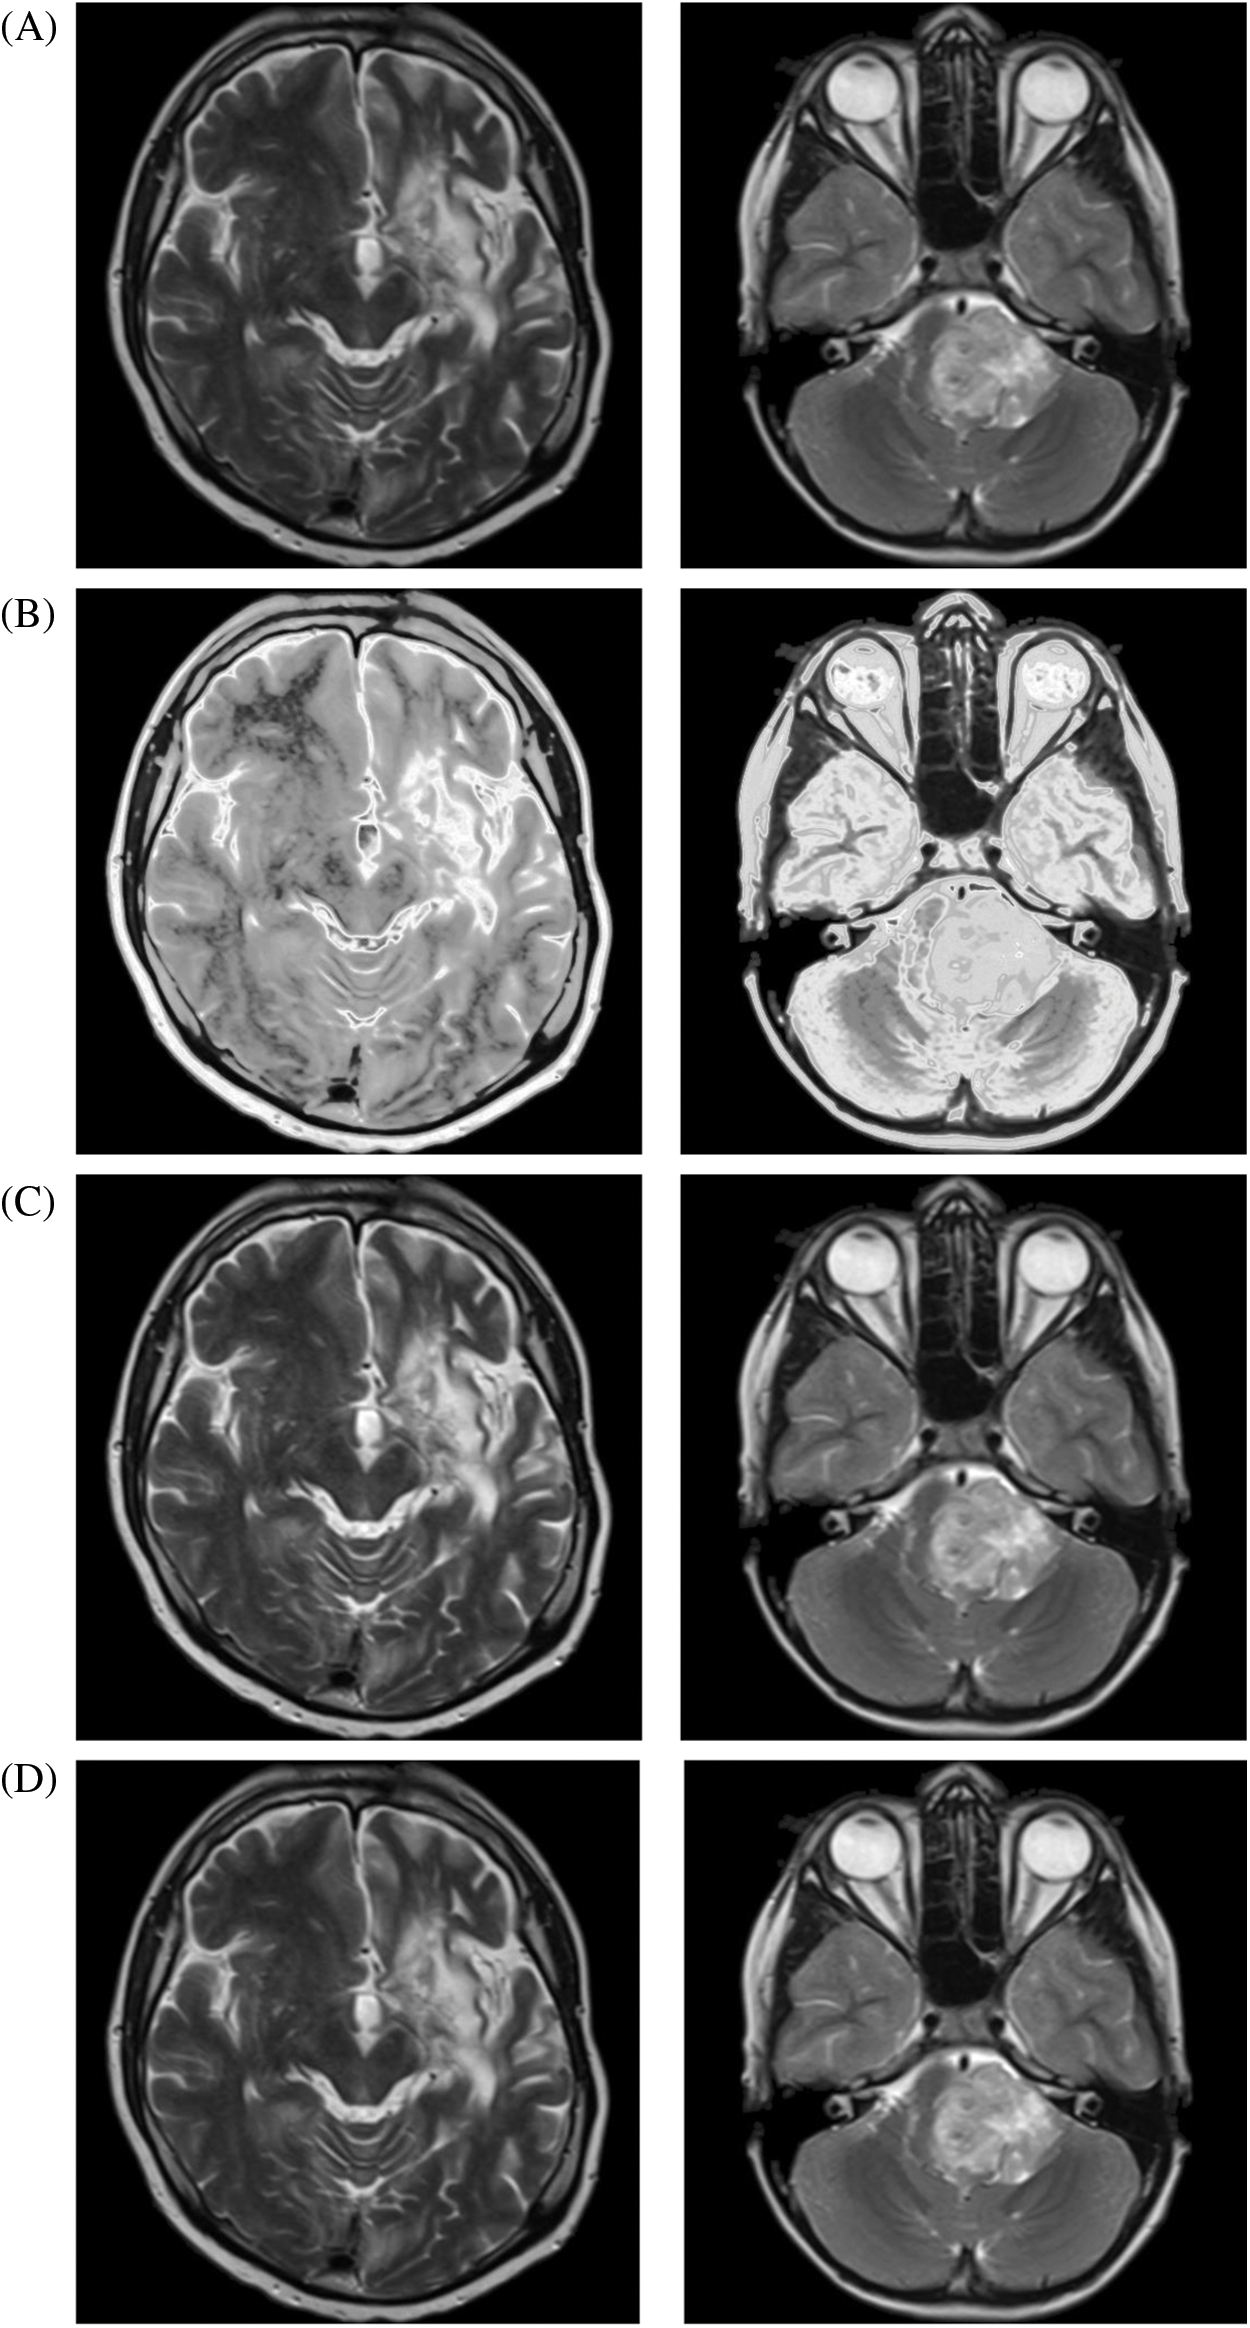

For the comparative analysis (Fig. 3), we used the following existing approaches to show that the proposed enhancement model is effective as a medical picture enhancing tool. Ibrahim et al. [3] developed an image enhancement approach for medical image improvement based on “fractional partial differential equations” (FPDEs). Aldawish et al. [6] proposed image enhancement model based on Mittag-Leffler sum convoluted with Chebyshev polynomial to improve images with low gray level changes by evaluating the probability of each pixel. Al-Shamasneh et al. [10] developed a fractional entropy-based approach for enhancing kidney images. Finally, a new fractional integral entropy based medical image enhancement approach that estimates the probabilities of imaging pixels was developed by [11]. In terms of image quality, the proposed method outperforms existing methods.

Figure 3: The proposed and existing enhancement models’ results on brain MRI. (A) Input image, (B) Ibrahim et al. [3], (C) Aldawish et al. [6], (D) Al-Shamasneh et al. [10], (E) Jalab et al. [11], (F) Proposed method